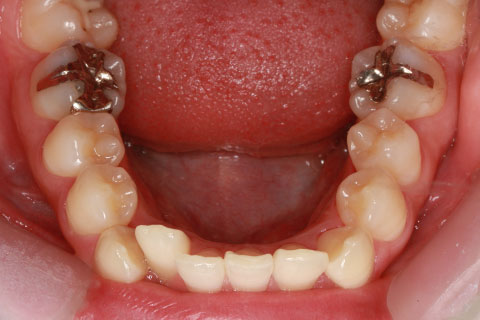

矯正期間24ヶ月

ハーフリンガル矯正3(上の歯のみ舌側矯正で治療)

治療前

治療中(開始直後)

治療中(開始半年後)

治療後

- 年齢・性別

- 25歳女性

- 治療期間

- 2年0ヶ月

- 抜歯

- 上下4番抜歯

- 治療費

- 110万円

- 備考

- 治療内容

- 施術の副作用(リスク)

- 表側矯正と比較して、力学的な操作性が複雑なため、ボーイングエフェクトを起こしやすい。